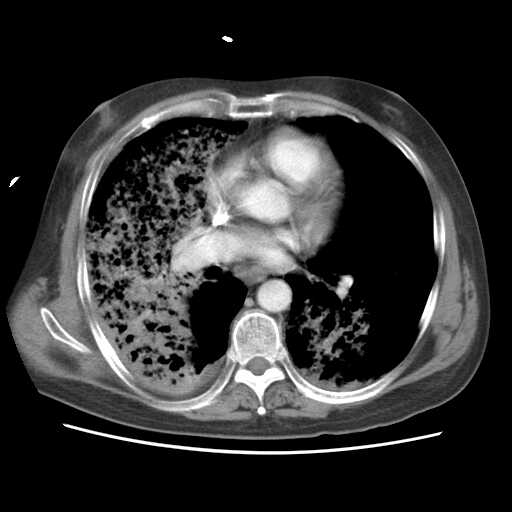

2008.8.17ct

病变从8.11-8.17明显改变,增多,以蜂窝状改变为主,类蜂窝肺,似弥漫性肺泡癌,但是病变进展太快,不符合弥漫性细支气管肺泡癌。因此考虑为特殊微生物感染,多以霉菌类常见,建议细菌微生物学检查。

疑点二:影象表现怪异,大片阴影内见多发筛孔征,如何解释.

结合临床慢支炎肺气肿,肺心病病史,三次胸片观察可见病情发展变化迅速,病情凶险,考虑多重感染伴ards.